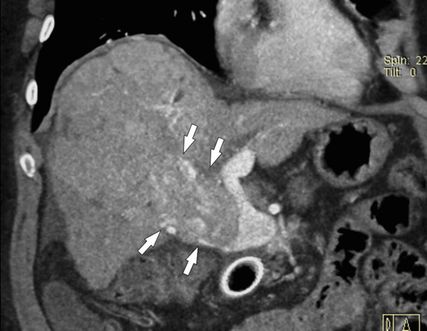

Abb. 2: Die Kontrastmittel-verstärkte MDCT (koronale 3D-Rekonstruktion) kann das Ausmaß einer PVT exakt abbilden: Die Thrombose ist nur im Pfortaderhauptstamm lokalisiert (Pfeil)

Die bildgebende Diagnostik stützt sich auf die farbcodierte Duplexsonografie (Abb. 1), die Kontrastmittel-verstärkte MDCT (Abb. 2) und die MRT, wobei die MDCT die höchste Aussagekraft hinsichtlich Ausdehnung der PVT und Darstellung möglicher Komplikationen hat. Wichtig ist bei der MDCT die Anfertigung von 3D-Rekonstruktionen des MDCT-Datensatzes zur besseren Darstellung der Thromboseausdehnung (Abb. 2), im Vergleich zur ausschließlichen Darstellung auf axialen Bildern.